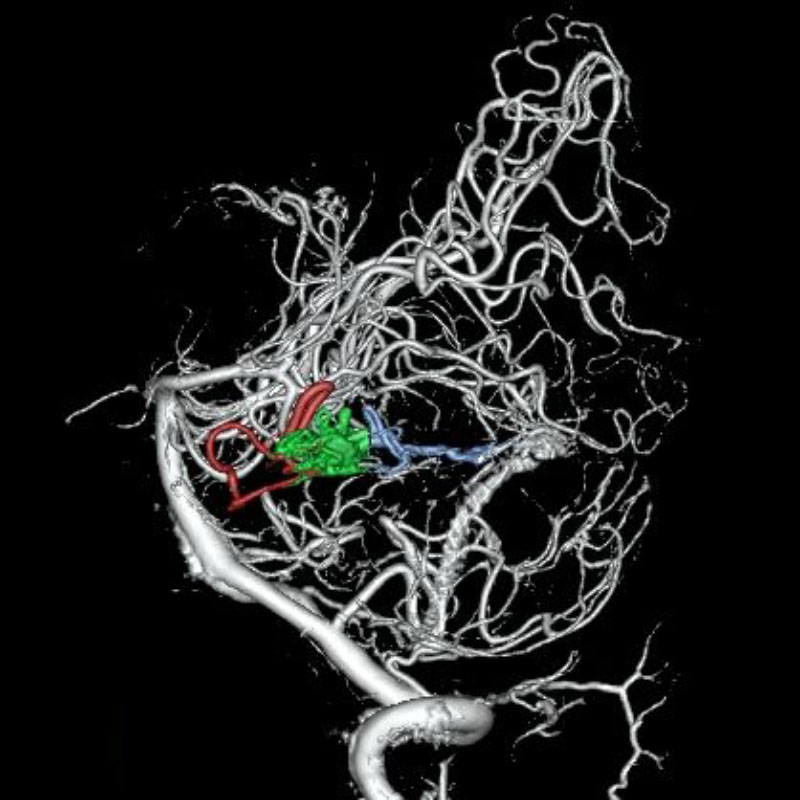

脳動静脈奇形

血管塞栓術

松田/濵田/元永